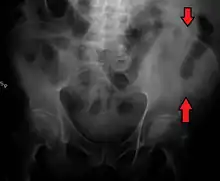

The crest of the ilium (or iliac crest) is the superior border of the wing of ilium and the superiolateral margin of the greater pelvis.

The iliac crest stretches posteriorly from the anterior superior iliac spine (ASIS) to the posterior superior iliac spine (PSIS). Behind the ASIS, it divides into an outer and inner lip separated by the intermediate zone. The outer lip bulges laterally into the iliac tubercle.[1] Palpable in its entire length, the crest is convex superiorly but is sinuously curved, being concave inward in front, concave outward behind.[2]

The top of the iliac crests also marks the level of the fourth lumbar vertebral body (L4), above or below which lumbar puncture may be performed. Furthermore, said level is often referred to as the "intercristal line".

Iliac crest labeled at center right